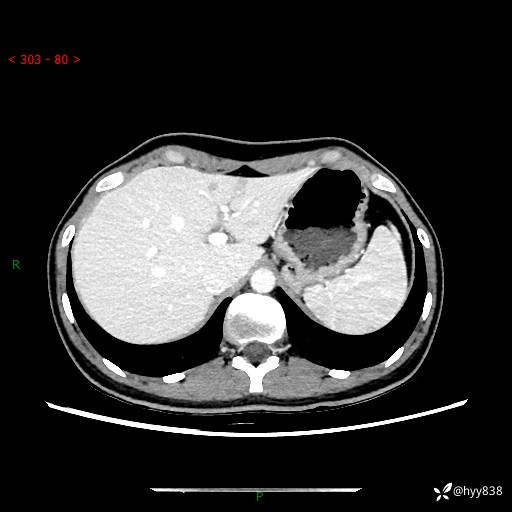

性别:女

年龄:23岁

简要病史:外院发现肝结节,来我院进一步增强确诊

上腹部CT平扫+增强